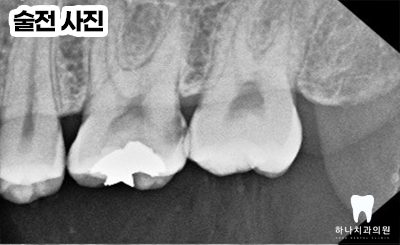

전체 x-ray 촬영 시 왼쪽 위 첫 번째 어금니에

까맣게 충치로 보이는 투과상을 발견하였는데요.

환자분께서는 불편함을 느끼지 않으셨지만

해당 인접면 우식을 해결하지 않는다면

순식간에 치아를 망가뜨릴 수 있는

부위임을 설명드리고 치료를 조심스럽게

권유 드렸습니다.

우식의 크기로 보았을 때

신경치료의 가능성을 배제하기에는

어려움이 있었지만 우식 부위 제거,

코어, 크라운으로 기능을 회복할 수 있도록

계획을 수립하였습니다.